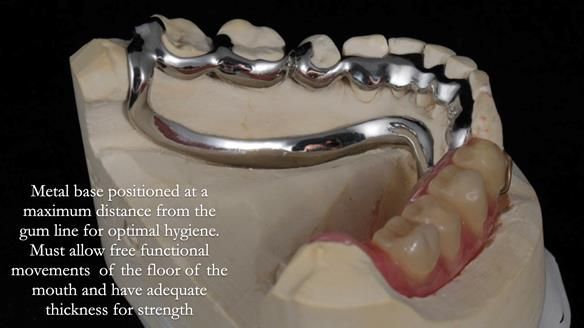

Welcome to Newsletter 61. In this edition, I walk through the process of creating and fitting a metal based lower partial denture for Joyce, a fit and healthy 76 -year-old woman.This issue shows the complete protocol workflow for achieving an exceptionally well-fitted and aesthetically good RPD.

Welcome to Newsletter 61. In this edition, I walk through the process of creating and fitting a metal based lower partial denture for Joyce, a fit and healthy 76 -year-old woman.

The missing lower right teeth to be replaced with a metal based partial denture.

The detailed clinical situation and treatment process are outlined below, with clinical work provided by me and technical work by Rowan Garstang. The treatment spanned six visits for denture fitting and one review.